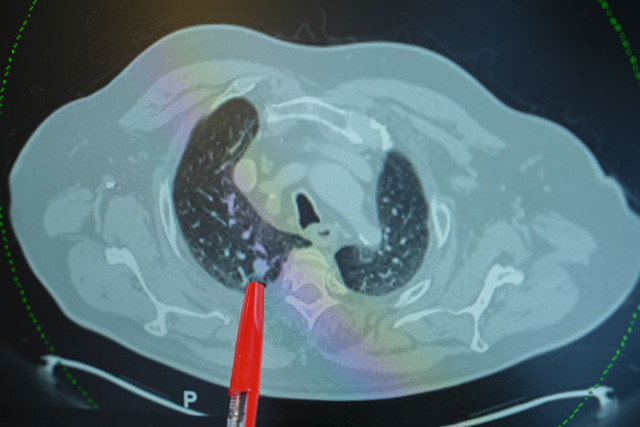

Pnömotoraks’ın akciğerin dış zarının yırtılmasıyla geliştiğini belirten Doç. Dr. Karapınar, “Bu durum, akciğer içindeki havanın göğüs boşluğuna kaçmasına yol açar. Kimi zaman kendiliğinden oluşabilir, kimi zaman ise dış etkenlere bağlı olarak gelişir. Özellikle sigara içen bireylerde, akciğerin zayıflaması sonucu risk daha da artar” dedi.

Pnömotoraks tedavisinde farklı yöntemler uygulandığını belirten Doç. Dr. Karapınar, hastalığın ilerleme seviyesine göre tedavi sürecinin değiştiğini ifade etti. “Eğer akciğer sönmesi küçük çaplıysa, oksijen tedavisi yeterli olabilir. Ancak daha ileri vakalarda göğüs tüpü yerleştirilerek hava tahliye edilir. Eğer akciğer ikinci kez sönerse, bu noktada cerrahi müdahale devreye girer. Kapalı yöntemlerle yırtılan bölge onarılır” dedi.